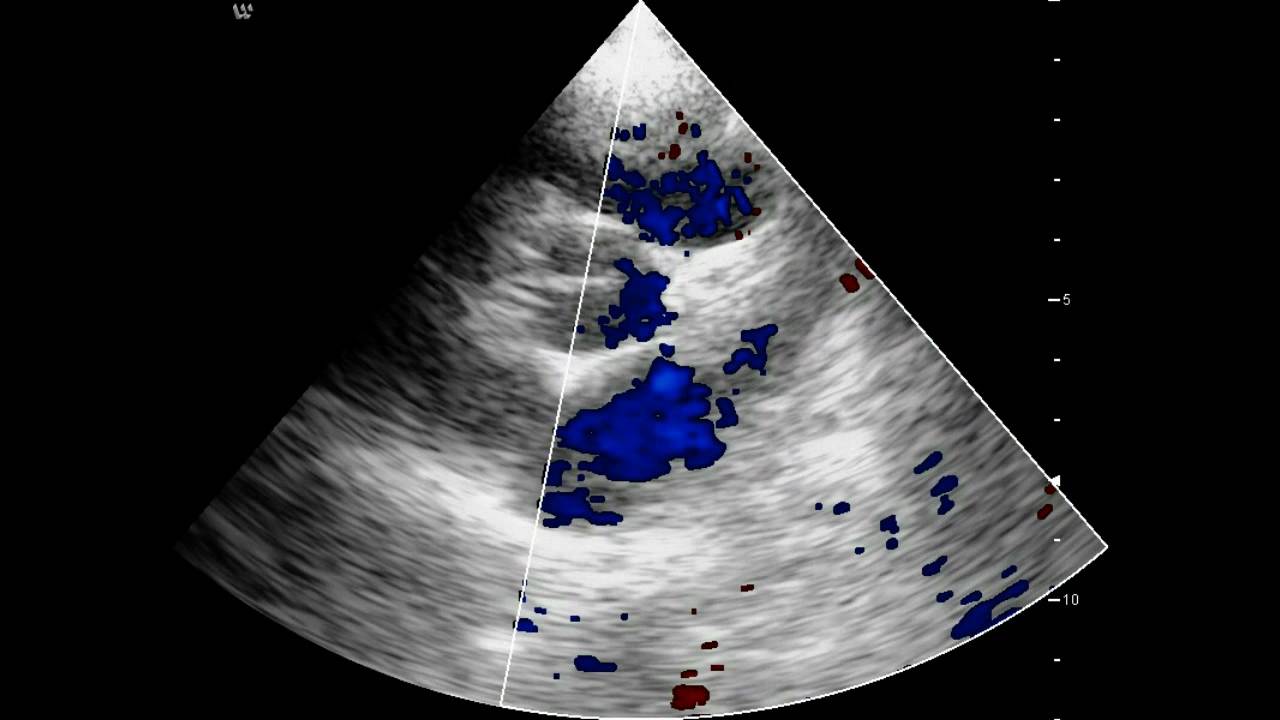

- Эхокардиографию.

Последние 3 метода позволяют визуализировать стеноз, определить его локализацию и степень выраженности.